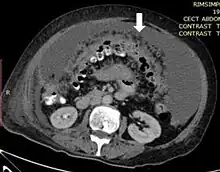

Axial abdominal computed tomography featuring omental caking due to peritoneal carcinomatosis | |

Omental cake is a radiologic sign indicative of an abnormally thickened greater omentum.[1] It refers to infiltration of the normal omental structure by other types of soft-tissue or chronic inflammation resulting in a thickened, or cake-like appearance.[2]

Due to the variety of symptoms experienced by patients with omental caking,[5] omental cakes are most frequently discovered on abdominal computed tomography (CT) or ultrasound. Plain film radiography (X-ray) is not a suggested modality for investigating the spread of cancerous cells in the abdomen due to the poor spatial resolution amongst soft-tissue densities. Contrast resolution obtained through CT allows radiologists to investigate omental caking for morphology, intraperitoneal fluid, and regional lymphadenopathy assists in proper diagnosis so clinicians, surgeons, and oncologists can plan the appropriate course of treatment.[8]